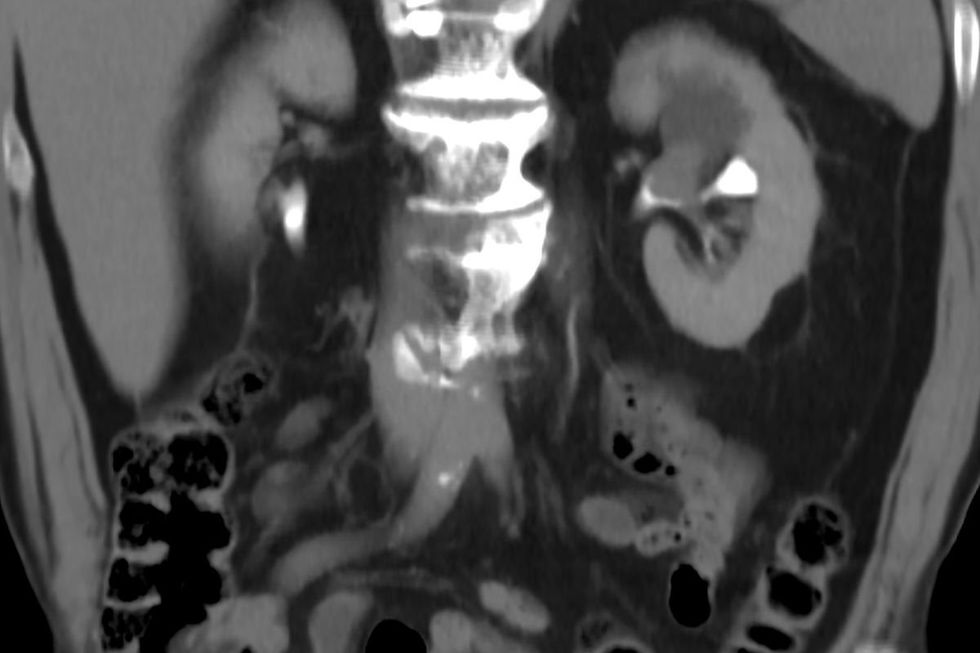

Back pain is one of the most commonly reported symptoms in the advanced stages of the disease

|GETTY

Those receiving a stage 4 diagnosis commonly presented with similar complaints - back pain (37 per cent), tiredness (34 per cent), blood in urine (26 per cent), and weight loss (26 per cent) - though 15 per cent remained entirely symptom-free.